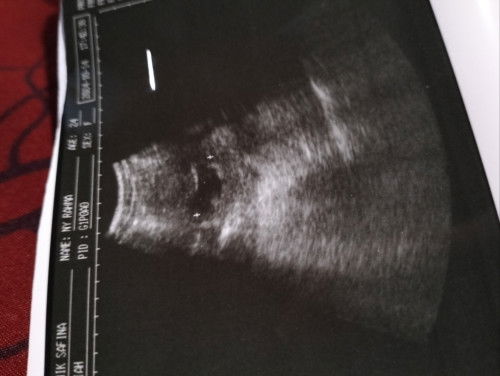

Izin tanya, kemarin udh USG yah bund ternyata usia kehamilan USG dgn yang di prediksi beda, di usia kehamilan di USG kemarin udh memasuki 6minggu 6 hari sedangkan prediksi tanpa di USG Bru memasuki 6 Minggu, Pertanyaanku kok bisa Bedaya usia kehamilan di USG dgn yang tanpa di USG oleh bidang, dan knpa yah sudah masuk 6 Minggu 3 hari kok blm ada janinya cuman kantongnya saja, dan kata dokter spesialisnya di suruh lagi cek 2 Minggu kedepan utk liat apakah sudah ada detak jantungnya atau belum. Apakah itu hal normal yah blm ada janinya dan detak jantung janinya di usia kehamilan segitu. #Sharing_dong_Bund #SeriusTanya #bantujawab #ingintahu